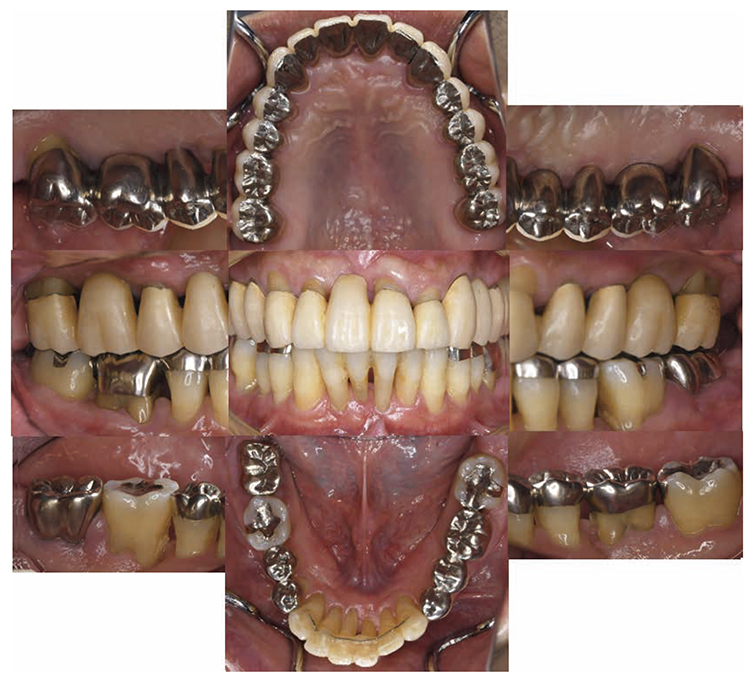

8)SPT (December 2013 onward)

After transitioning to SPT, the patient brushed 4 times daily after every meal and before bedtime and has continued to use an interdental brush. PCR levels have been consistently in the 20% range. SPT , which primarily consists of instructions on brushing and dental surface cleaning, has been implemented every other month to present, and efforts are made to maintain and manage oral hygiene in the long term to ensure that plaque control is not insufficient. While minor discoloring is observed on the prosthetics, the color of the gingiva is salmon pink and a macroscopically healthy appearance has been sustained (Fig.7a) . The average PD on the entire jaw is 2.1mm,maximum PD is 4.0mm,the ratio of PD of 3mm or less is 99.3%. No BOP has been found and the condition of the periodontal tissue has been stable (Fig.7b). In the X-ray, continuity of the alveolar hard line has been replicated and the sequence of the bone trabeculae has been normal (Fig.7c).

Fig 7a

(Fig.7a) Intraoral photo: 15 years after first visit (December 2022)

Fig 7b

(Fig.7b) Examination for reevaluation: 15 years after first visit (December 2022)

Fig 7c

(Fig.7c) 15 years after first visit: dental X-ray 14 (December 2022)